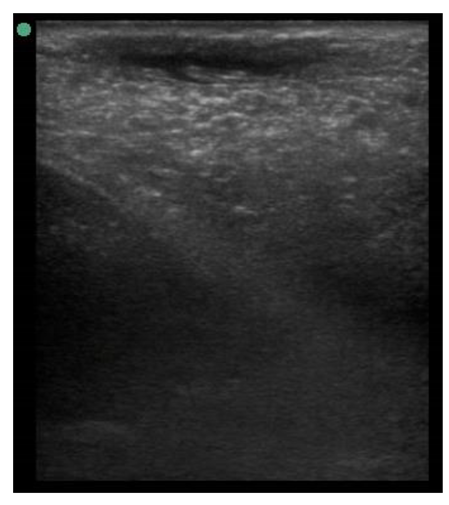

| 109 days of pregnancy (P109) Scanning depth 4.7 cm | ![]() | ![]() | MT generous: 36.8 mm MT conservative: 27.2 mm Gland cistern: 4.7 mm Parenchyma: 15.4 mm Fat Pad: 5.5 mm |